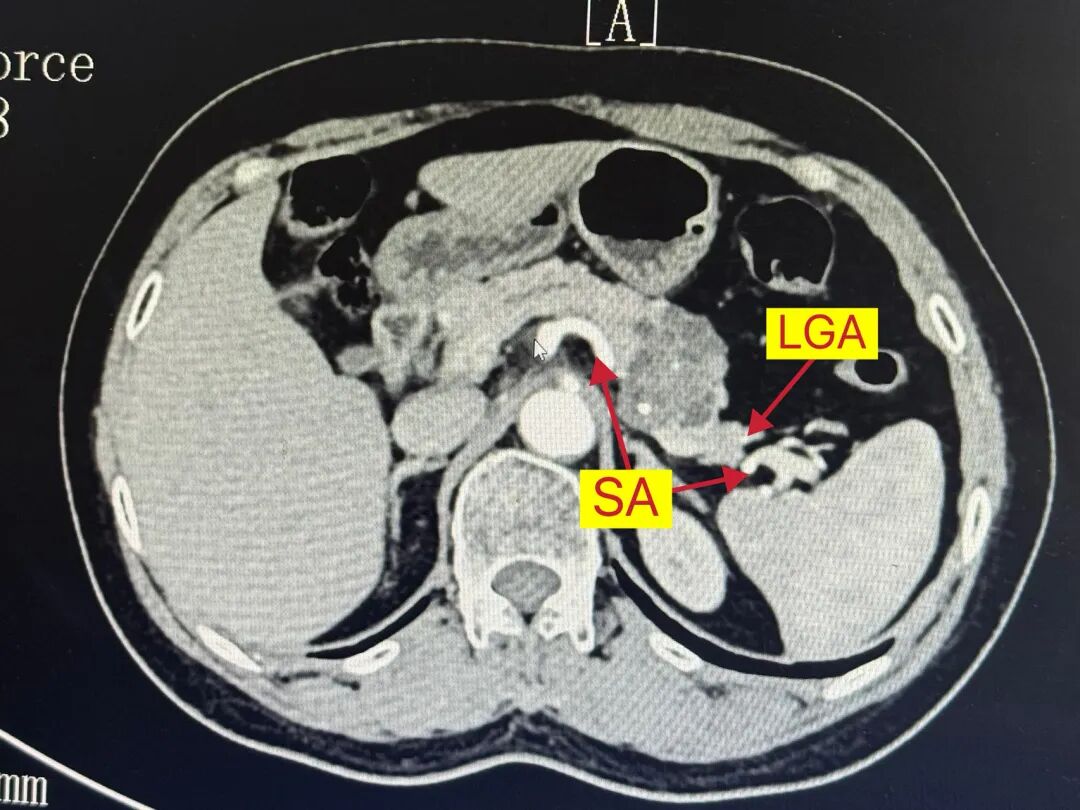

术前影像学评估及规划:MRI上呈多囊型、“蜂窝征”,中央钙化,我的初步印象符合SCN浆液性囊腺瘤“奶奶瘤”的表现。做Kimura还是Warshaw?CT增强看到肿瘤几乎将脾动静脉完全“吃”进去,但肿瘤距离LGA和SA在脾门的汇合点有一定距离。我知道Kimura很好,但在腔镜下剥离脾静脉带给我的多是一些不太美妙的回忆,而且从我做Warshaw的经验看,患者普遍恢复得不错。

我们按照LPD经典的笑脸五孔法建孔,做胰腺不管是LPD还是LDP,我都这么打。打开大网膜时,保护胃网膜动脉弓,处理脾门时在LGA与SA汇合点之前离断胰尾,在预定胰腺切断线稍内侧分离过7号线,以切割闭合器切断胰腺及脾血管,手术结束,患者恢复顺利,随访1年状态很好。